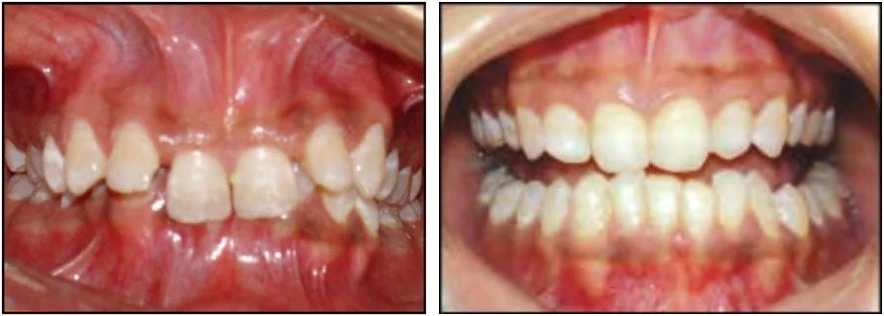

Cắn hở

Với loại này thì không có độ phủ hoặc chỉ có một khoảng trống giữa các răng hàm trên và hàm dưới khi bệnh nhân cắn lại ở khớp cắn trung tâm. Một trường hợp cắn hở có thể gặp ở răng trước hoặc răng sau.